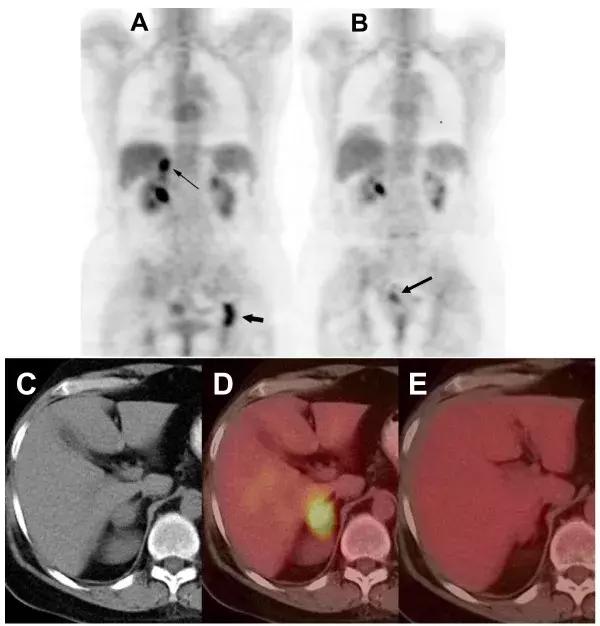

肝癌

对41例晚期肝细胞癌(HCC)进行测试,患者每天经过3次电场治疗,每次60分钟,4名患者有客观反应(包括2名持续响应近5年),14名患者病情稳定超过6个月。中位PFS为4.4个月(95%CI,2.1-5.3个月),中位OS为6.7个月(95%CI,3.0-10.2个月).